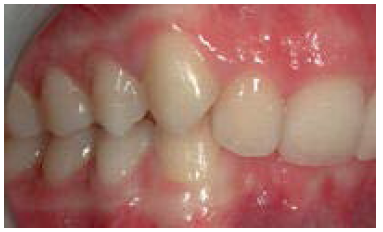

The maxillary first molar is forward of the normal molar relationship in Class II. The mesiobuccal cusp of the maxillary first molar is mesial to the buccal groove of the mandibular first molar. In Class II Division 1 (Figure 2), the maxillary incisors are in labio-version, or protruding. In Class II Division 2 (Figure 3), the maxillary central incisors are in linguo-version (retruded) and lateral incisors are protruded. In Class III the maxillary first molar is distal of the normal molar relationship. The mesiobuccal cusp of the maxillary first molar is distal to the buccal groove of the mandibular first molar.

Figure 3. Class II Division 2.

Figure 3